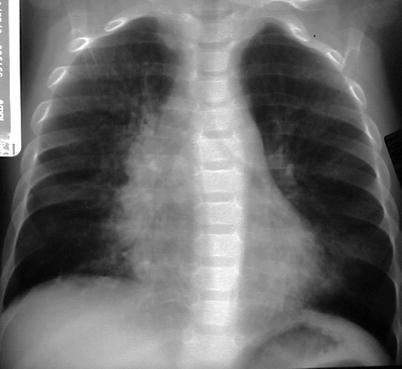

Children represent 2 % of the reported cases of human immunodeficiency virus (HIV) infection. Most children are infected after vertical transmission from their mother, and majority develop acquired immunodeficiency syndrome (AIDS) early in life. There is increased susceptibility to bacterial, viral, fungal, protozoal, and opportunistic infections. Lobar or segmental consolidations are the most common patterns (Marks et al. 1996). Mycobacterial infection can be seen in AIDS patients, and the radiographic appearance mimics that seen in immunocompetent children with primary tuberculosis. Mycobacterium avium-intracellulare is also encountered later in the course of disease and imaging findings cannot be distinguished with other forms of mycobacterial infections (Collingsworth 2005). Pneumocystis jiroveci is the most common opportunistic pulmonary infection in children with AIDS, occurring in up to 50 %, and is the leading pulmonary cause of death (Jeanes and Owens 2002). Radiographic appearances are variable and include hyperinflation with diffuse bilateral interstitial or nodular infiltrates from the perihilar region to the periphery, which often progresses to widespread alveolar opacities with air bronchogram (Fig. 13.30). Cavitary nodules and cysts can be seen, with pneumothorax and/or pneumomediastinum as common complications. HRCT findings include patchy or diffuse ground-glass opacity, consolidation, cyst or cavities, centrilobular opacities, nodules, peribronchial cuffing, and interlobular septal thickening (Jeanes and Owens 2002; Collingsworth 2005).

Fig. 13.30.

Pneumocystis jiroveci infection. Radiograph of a 10-month-old boy diagnosed with severe combined immune deficiency syndrome showing diffuse reticulonodular interstitial pattern in both lungs with development of lung consolidations (a). Radiograph of a 14-month-old girl with HIV infection showing diffuse, bilateral interstitial lung pattern extending from the hilum (b). There is a cyst noted on the peripheral right lung (arrow)